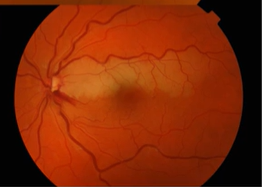

Name the condition

Retinal Vein Occlusions- CRVO, BRVO, Hemi-retinal Vein Occlusion

Describe the picture

BRVO

Only ½ of retina affected-macula affected

Depending on which venous branch is affected through the occlusion macula may be spared